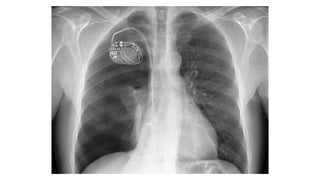

A 61-year-old man presented with worsening right thoracic pain and dyspnea three days after being discharged from cardiology following pacemaker implantation for sick sinus syndrome. A 60-year-old woman with an implanted pacemaker presented with dizziness and fainting. A 77-year-old woman who had a pacemaker implanted for symptomatic sinus bradycardia presented one week later with continuous chest pain. An elderly patient presented 6 months after pacemaker implantation with a recurrence of exertional shortness of breath.